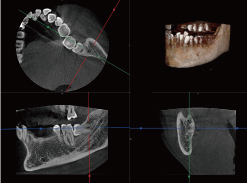

歯科用CTによる3D画像診断